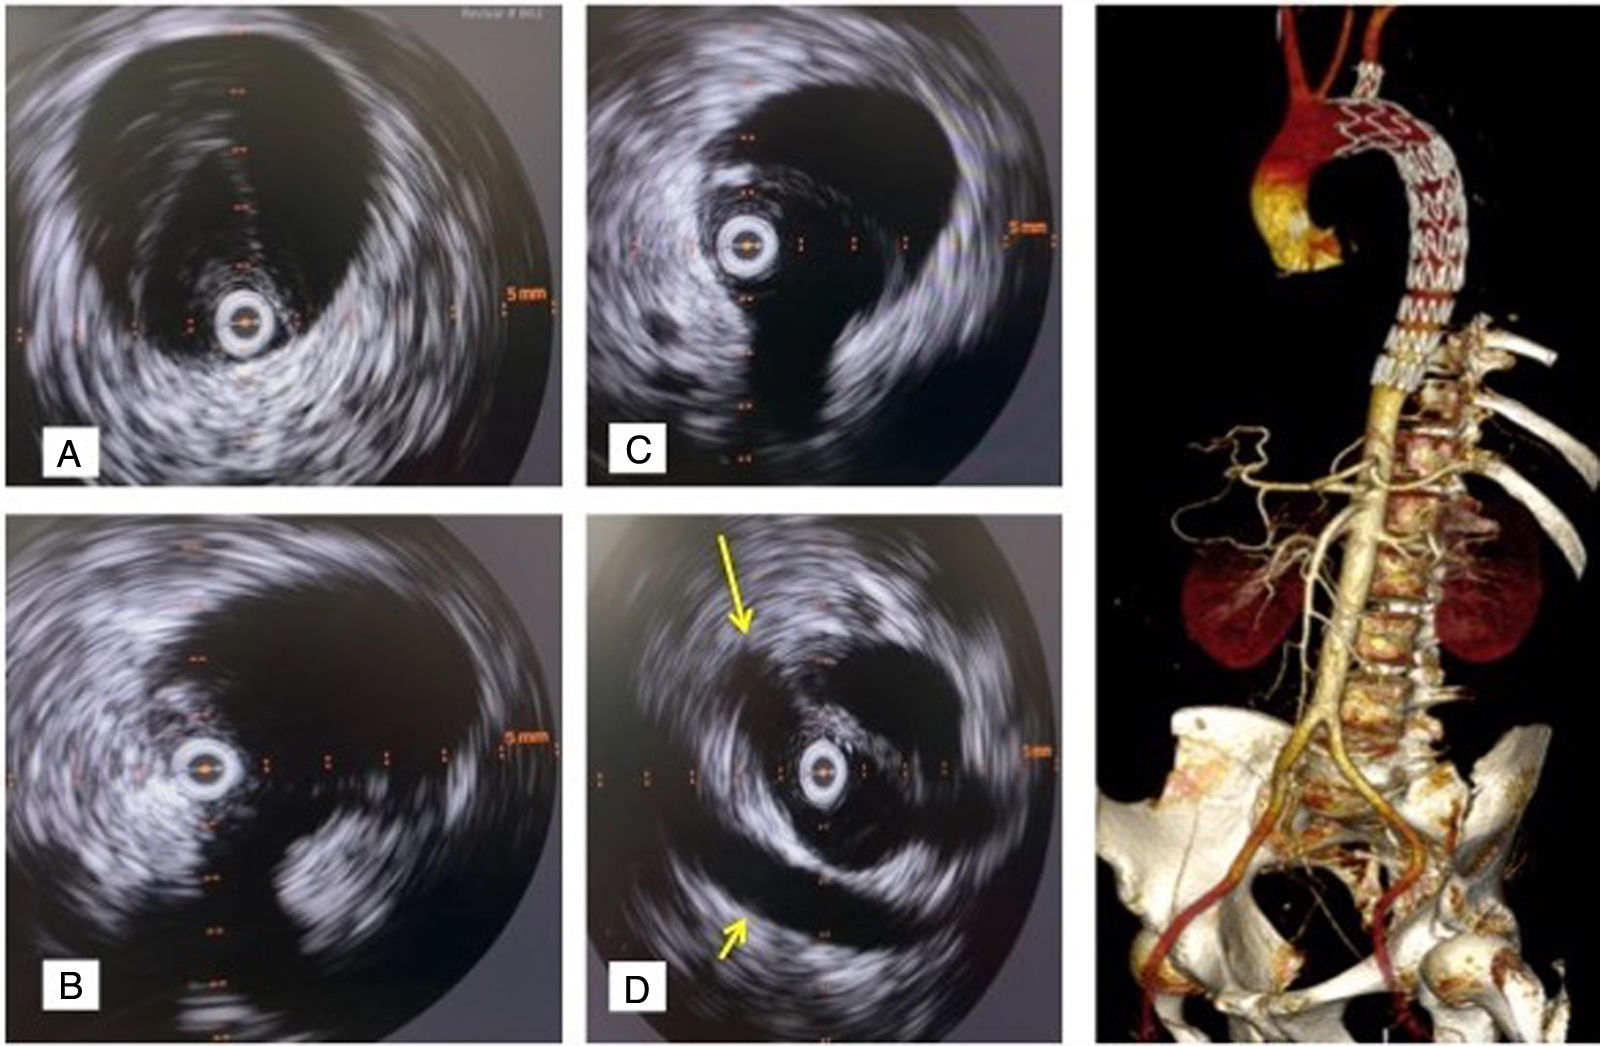

IVUS verificando normoposición de guía en VL previo a implante endoprótesis en disección aorta tipo B subaguda (caso 3): A) IVUS a nivel aorta torácica distal. B) IVUS a nivel de tronco celíaco. VL casi colapsada. C) IVUS a nivel de arteria mesentérica superior. D) IVUS a nivel de arterias renales, ambas saliendo de VL. Arteria renal derecha (flecha larga), vena renal izquierda (flecha corta). E) Tomografía axial computarizada en el postoperatorio inmediato: reconstrucción 3D (volume rendering). Origen de troncos viscerales desde VL y adecuada expansión VL. Arco bovino. IVUS: intravascular ultrasound; VL: verdadera luz.